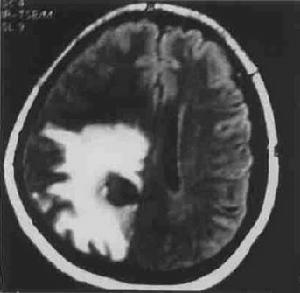

頂葉腫瘤CT圖(二)腦膿腫頂葉腦膿腫的發生率較顳、額葉不見,多為血源性感染,急性期多有全身性表現(高熱、周圍血像多形核白細胞增多)和急性顱內壓增等,腰穿顯示腦脊液有化膿性改變,很容易與腦瘤鑑別診斷。但頂葉慢性腦膿腫病程較長,其臨床症狀與頂葉腫瘤相似多數難以鑑別只有手術探查時才能明確診斷。